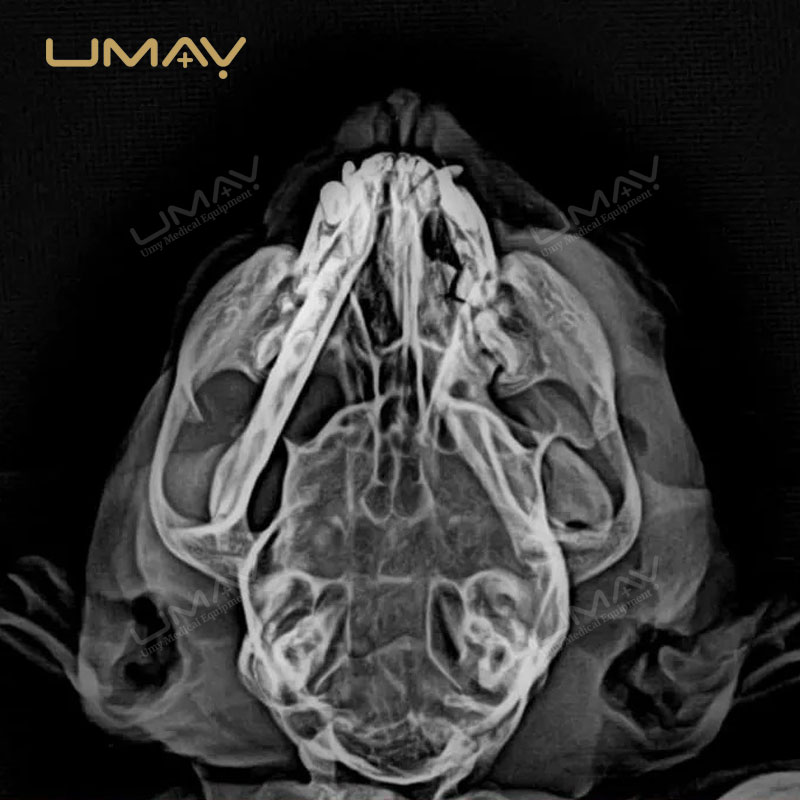

El detector digital de panel plano 1417 para radiología veterinaria está diseñado para proporcionar imágenes de alta resolución que permiten diagnósticos precisos en una amplia variedad de animales. Su avanzada tecnología DR garantiza una captura rápida y eficiente, reduciendo la exposición a la radiación sin comprometer la calidad de imagen.

Gracias a su diseño ligero y portátil, este detector se integra fácilmente en sistemas de rayos X veterinarios existentes, lo que lo convierte en una opción ideal tanto para clínicas fijas como para servicios móviles. Su versatilidad permite realizar estudios radiológicos en animales pequeños, medianos y grandes, optimizando el flujo de trabajo en entornos de alta demanda.